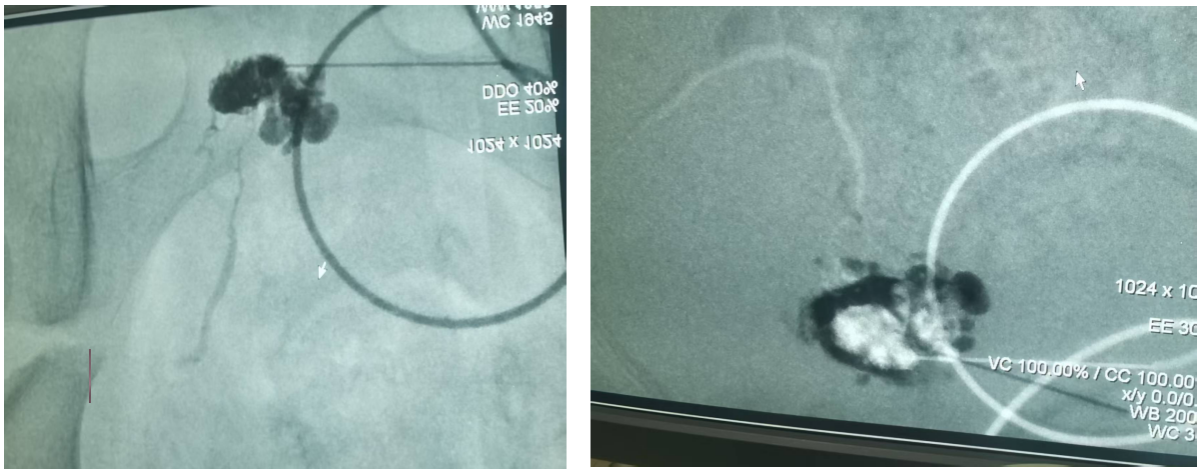

3.血管瘤与脉管畸形介入手术

2. 血管瘤灌注治疗

1.聚桂醇注射治疗淋巴管瘤